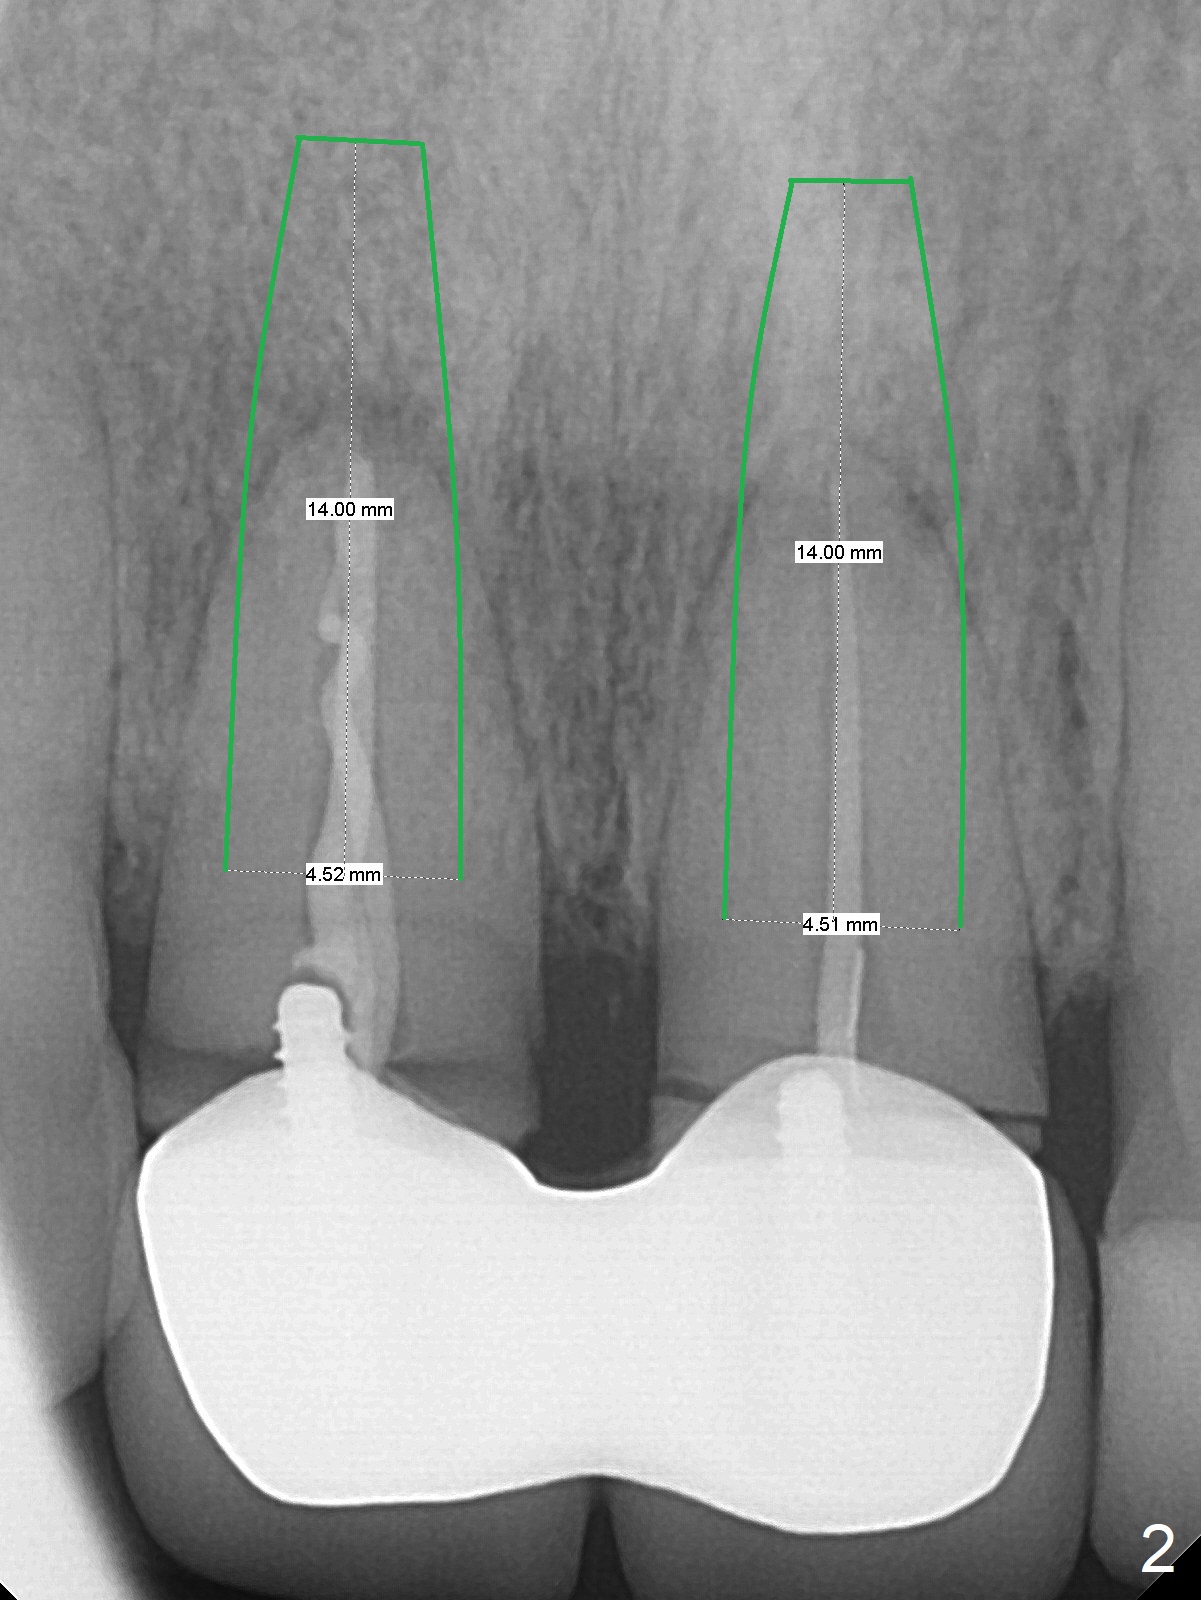

A 36-year-old woman fractures the teeth 8 and 9 while the implant at #3 is healing (Fig.1 arrowheads). It appears that the teeth are wide enough to accept 4.5x14 mm implants (Fig.2).